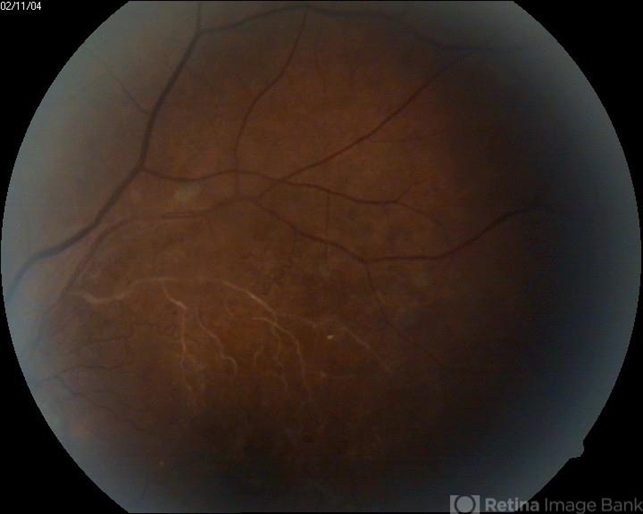

- Eales disease

- A 30-year-old male presented complaint of gradual loss of vision OU and picture was like this.